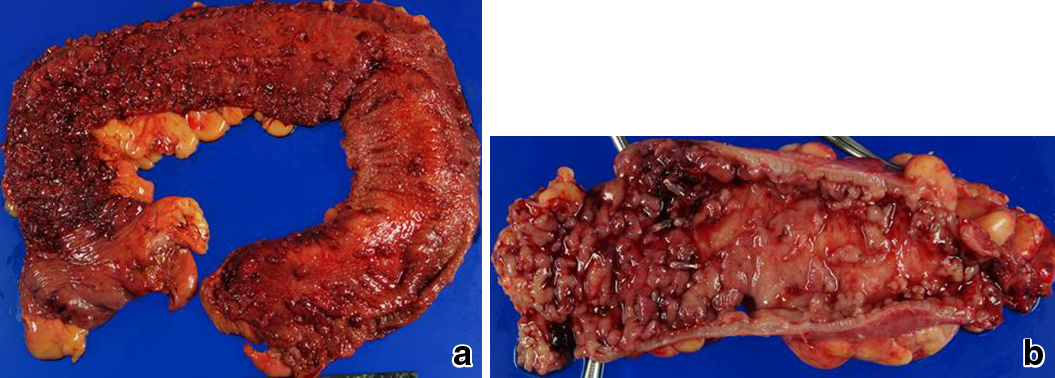

術前経過:前医入院1か月前に下痢と血便が出現した.前医受診後,潰瘍性大腸炎,重症と診断され入院となった.ステロイド大量静注療法,白血球除去療法を施行し,排便回数は減少傾向であったが,入院35日目,突然に大量出血し出血性ショックとなったため緊急手術目的に当科へ転院した.Alb 1.2 g/dlと低栄養状態で,肛門管に深い潰瘍を認めたため結腸亜全摘術,S状結腸粘液瘻造設,回腸人工肛門造設術を行った(Fig. 2a).

a, b: Resected specimen of the colon showed multiple deep ulcers involving the muscle layer and relative sparing of the sigmoid colon. While the muscle layer was widely exposed, hardly any mucosa remained in the rectum.

術後経過:術後3日目に突然,残存大腸から大量に出血し,収縮期血圧が60 mmHgまで低下したため,緊急手術を行った.

第2回目手術:腹腔内の高度な炎症や癒着は認めなかったため再建は可能であると判断し,残存大腸切除,IACAを行った(Fig. 2b).また,肛門管に深い潰瘍が残存しており縫合不全のリスクを考慮し,一時的回腸人工肛門を造設した.

術前経過:前医受診1か月前に下痢が出現,前医受診後に重症潰瘍性大腸炎と診断され入院となった.ステロイド大量静注療法で改善しなかったため当院に転院となった.入院時の腹部CTで横行結腸の著明な拡張と壁の菲薄化,free airを認め,中毒性巨大結腸症,穿孔性腹膜炎の診断で同日緊急手術を行った.横行結腸穿孔に伴う急性汎発性腹膜炎のため結腸亜全摘,S状結腸粘液瘻造設,回腸人工肛門造設術を行った(Fig. 3a).

a, b: Resected specimen of the colon showing hardly any mucosa remaining, especially in left side of the colon, and dilation of the colon because of the thin muscle layer. In the resected rectum, the muscle layer was broadly exposed.

術後経過:術後4日目から少量の粘血便が持続し,粘液瘻から水様性プレドニゾロンの注入を行った.術後11日目に出血が増加したが,出血性ショックには至らなかったため下部消化管内視鏡検査を行った.残存大腸の広範な潰瘍から出血を認め,最も出血の多い潰瘍を同定してclippingで止血した.術後24日目に再度,出血が増加し内視鏡下に数か所clippingしたが止血が不十分なために術後25日目に準緊急手術を行った.

第2回目手術:腹膜炎後で高度の癒着を認め,さらに肝硬変の合併もあったことから再建は行わず,直腸部分切除,Hartmann手術を行った.術中内視鏡を行い,出血点が切除側に含まれることを確認し,腹膜翻転部口側2 cmで残存大腸を切除した.

第2回目手術後経過:再出血なく経過し退院となり,2回目手術から6か月後,残存直腸全摘術,IACAを行った(Fig. 3b).回腸囊機能状態となってから3年11か月経過した現在,全身状態も良好で,外来通院中である.